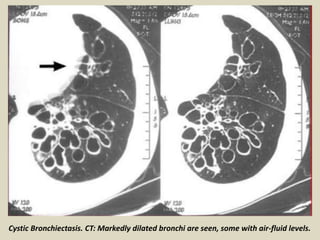

Cystic Bronchiectasis. CT: Markedly dilated bronchi are seen, some

with air-fluid levels (yellow arrows), mostly in the right lung.

Cystic Bronchiectasis. CT: Markedly dilated bronchi are seen, some with air-fluid levels.